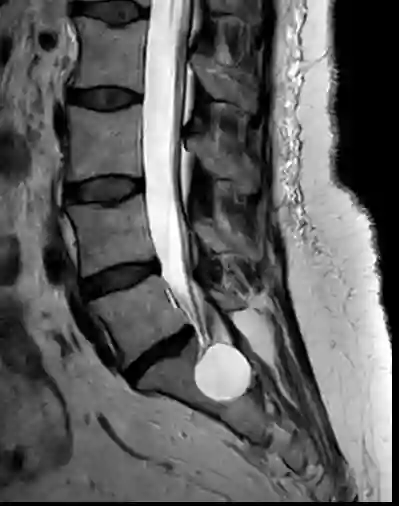

Sacral perineural cyst

Visualization of a sacral perineural cyst in a sagittal T2 sequence in the sacral region.